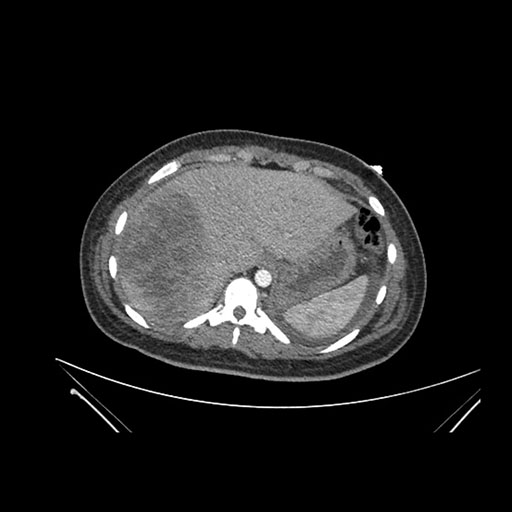

Axial Arterial

Axial Venous